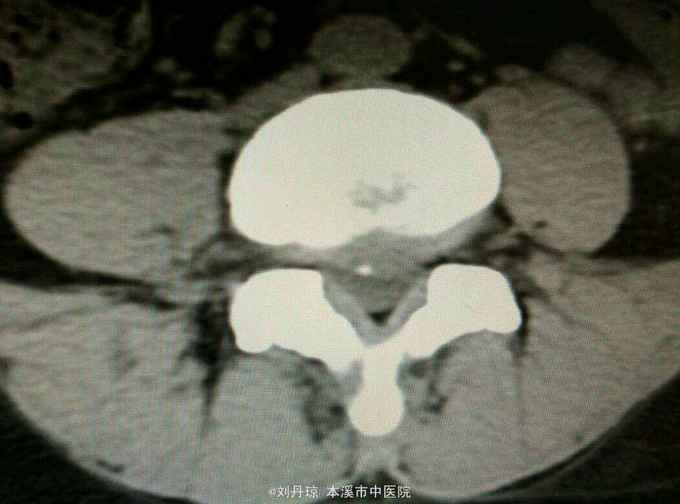

腰部疼痛伴右下肢放射痛麻木感1年,加重1月。患者1年前劳累后感到腰部疼痛伴右下肢放射痛麻木感,近1月病情加重来诊。

查体:L3—S1棘突右旁压痛阳性。直腿抬高实验左70度,右40度。 直腿抬高加强实验左侧阴性,右侧阳性。腰椎功能障碍。 辅查:CT: L3—S1椎间盘突出。

诊断:腰椎间盘突出症 治疗:针灸、雷火灸、中药熏药治疗、小针刀治疗、骶管注射治疗、营养神经药物治疗、脱水药物治疗,当归地黄饮加味。